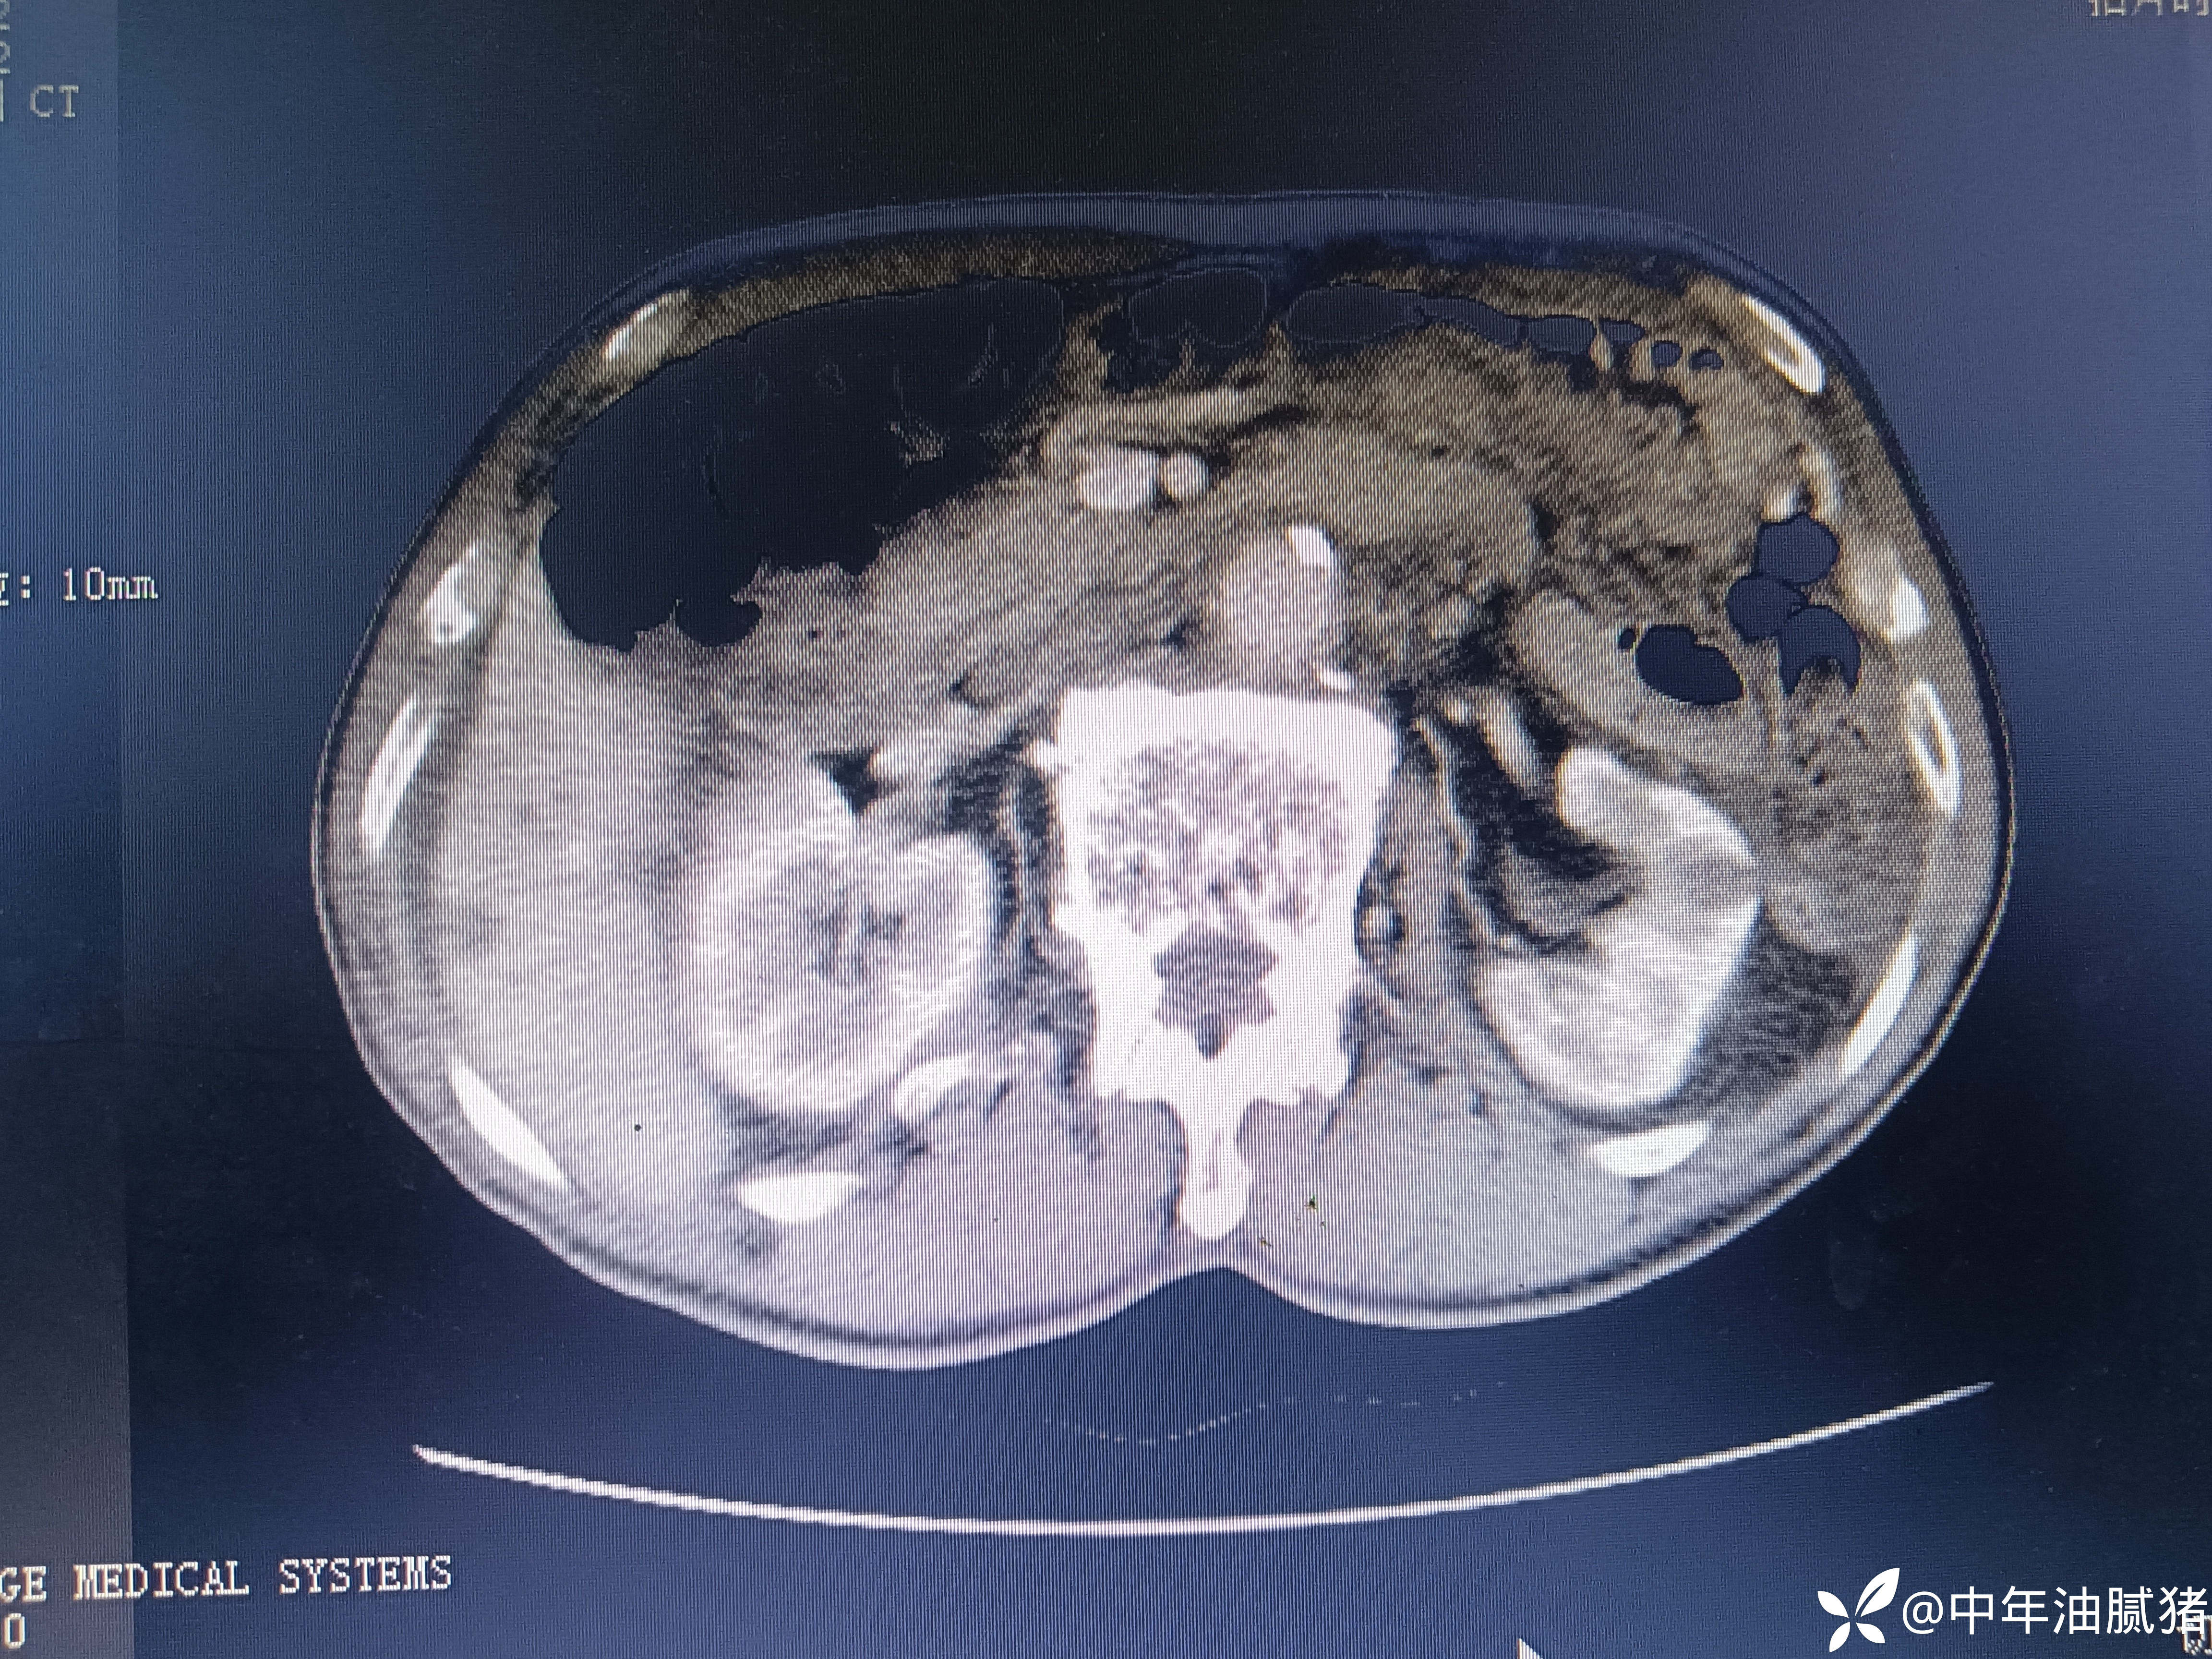

肺ct看到肝内病灶,行增强检查

建议增强ct.报告如下

考虑肝囊肿?让他走?

看后,我隐隐约约觉的不是肝囊肿那么简单?元芳,你怎么看?狄阁老,我也是这么认为!摇人,掏起手机:喂,w主任,请帮我看看这个ct。5分钟后报告修改如下